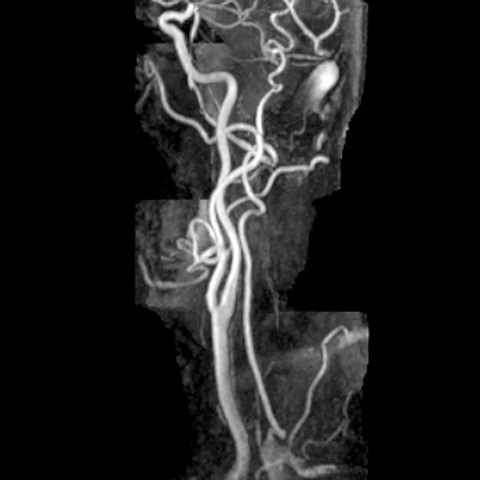

Carotid arteries (normal) [5 of 5]